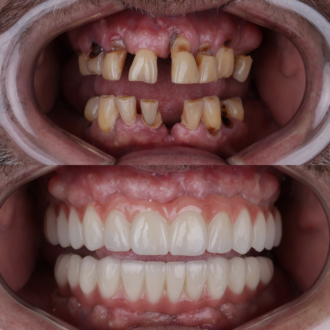

Процедура імплантації – це швидкий, сучасний та безпечний метод відновлення архітектури усмішки. Ще 10 років тому з процедурою асоціювалось безліч упереджень та побоювань. Але сьогодні в арсеналі лікарів є велика добірка атравматичних методик, матеріалів та методів реабілітації, які роблять імплантацію абсолютно рутинною процедурою. У мережі стоматологій РЕФЕРТА процедура імплантації виконується за сучасними протоколами з використанням преміальних матеріалів. Ви можете бути впевнені у виключній безпеці виконання та сяючому результаті процедури.

При негайній одноетапній процедурі імплантат встановлюється в кістку відразу після видалення зуба, а на абатмент імплантату встановлюється тимчасова коронка. Тимчасова коронка замінюється на порцелянову коронку після періоду повного приживлення імплантату. Цей варіант процедури є менш травматичним для кісткової тканини та має значно менший період відновлення. Лікарі РЕФЕРТА досконало володіють цією методикою, завдяки чому наші пацієнти значно скорочують свій шлях до омріяної усмішки.